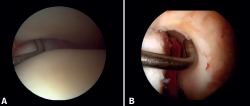

Evaluación artroscópica de la sindesmosis

Desde el portal anteromedial tenemos una visualización directa de las fibras distales del LTPA. Una desinserción de estas fibras no se traduce siempre en inestabilidad de la sindesmosis, pero nos obliga a comprobarlo. Los autores preferimos la evaluación del plano coronal de la sindesmosis. Introducimos el artroscopio en la articulación tibioastragalina dirigiendo la cámara hacia craneal. De este modo, tenemos una visión directa de la articulación tibioperonea distal. Entonces evaluamos la estabilidad intentando introducir el palpador en la articulación. Si es posible hacerlo, catalogamos la lesión de la sindesmosis como inestable (Figura 6A).

Evaluación artroscópica del ligamento deltoideo

Existen múltiples métodos para evaluar la inestabilidad del complejo medial; mediante los portales anteriores del tobillo es posible valorar la estabilidad del ligamento deltoideo en su plano principal de acción, correspondiente al plano coronal. Chun et al.(20) describió inestabilidad cuando es posible introducir un palpador artroscópico en el espacio medial tibioastragalino (Figura 6B). Vega et al.(21) describió que, en la mayoría de las lesiones, la porción más anterior del ligamento deltoideo está desprendida del maléolo medial, mientras que sus inserciones proximales permanecen íntegras. En esta situación se puede introducir el palpador artroscópico entre la pared medial del maléolo interno y las fibras profundas del deltoideo.

Técnica quirúrgica: tratamiento artroscópico de las lesiones agudas de la sindesmosis

La técnica se realizará utilizando los portales anteromedial y anterolateral convencionales. El portal anteromedial se emplea para la visualización, mientras que el portal anterolateral sirve como portal de trabajo. Una vez visualizado el espacio tibioperoneo, resecaremos la sinovial inflamada con un shaver artroscópico para facilitar la reducción (Figura 7A). Posteriormente, mediante visión directa restauraremos el espacio tibioperoneo, teniendo muy en cuenta la posible malrotación del peroné, especialmente en fracturas de tipo Maisonneuve. Para la reducción peronea utilizamos una pinza de tipo Verbrugge que nos permite corregir la rotación. En nuestra experiencia, una vez limpiado el espacio y si la posición es correcta, es poco frecuente tener que utilizar una pinza compresora entre tibia y peroné.

Figura 6. Maniobras para evidenciar inestabilidad ligamentosa. A: lesión de la sindesmosis que permite la introducción del palpador en la tibioperonea distal; B: lesión del deltoideo que permite la introducción del palpador en el espacio medial tibioastragalino.

Figura 7. A: desbridamiento del espacio tibioperoneo; B: estabilización de la sindesmosis mediante sistema de suspensión.